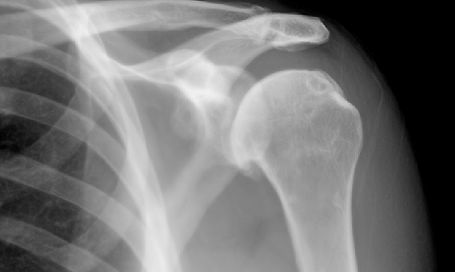

Shoulder Pain

Do you suffer from shoulder pain? The shoulder is the body’s most mobile joint, making it prone to a wide variety of injuries and conditions. Common causes of shoulder pain include neck and upper back issues, arthritis in the shoulder joint, abnormal motor patterns causing improper movement, participation in sports, and car accidents. Fortunately, our Centerton chiropractic clinic is here to help.

Shoulder pain or restricted motion can develop gradually over time or appear suddenly, depending on the cause. Since the shoulder is involved in most of our daily activities, any injury or discomfort should be taken seriously. Even minor injuries should be treated early to prevent them from worsening.

As with any condition, effective treatment for shoulder pain depends on identifying its exact cause. That’s why an accurate diagnosis is critical. At Ozark Family Chiropractic, our team is fully trained and equipped to diagnose the root cause of your shoulder pain. Using a combination of your medical history, advanced imaging techniques, and orthopedic assessments, we can pinpoint the underlying issue.

Chiropractic care has been proven to be highly effective for many shoulder conditions. At Ozark Family Chiropractic, our chiropractors start by evaluating the spine, with a focus on the neck region. The muscles and structures that control the shoulder joint originate in the neck and upper back. If spinal misalignments interfere with the communication between nerves and the structures they regulate, a cascade of issues can arise. Additionally, research shows that many cases of shoulder pain are actually referred pain originating from the neck.

If shoulder pain persists after correcting spinal misalignments, our experienced chiropractors at Ozark Family Chiropractic can provide targeted adjustments to the shoulder joint itself. We often combine chiropractic care with manual and passive therapies to promote faster recovery and optimal results.

Whether your pain stems from spinal issues or damage to the shoulder joint, chiropractic care offers a non-invasive and effective treatment option. Contact Ozark Family Chiropractic in Centerton today to find out how chiropractic care can help you.